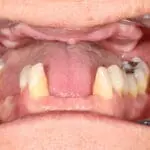

Our patient arrived at Flax Dental with a complex set of challenges. A prior dental experience had left her with an ill-fitting lower denture, missing front teeth, and a smile that no longer reflected her vibrant, outgoing personality. The issues she faced were both aesthetic and functional:

- Unstable Dentures: Her loose lower dentures caused anxiety during meals, forcing her to eat alone in her car to avoid public embarrassment.

- Over-Prominent Canines: Her previous denture design made her feel self-conscious, describing her lower teeth as “dog-like.”

- A Dull, Gummy Smile: The immediate denture provided no vibrancy, making her smile appear unnatural and lifeless.

This was not just a dental challenge—it was a deeply personal issue that affected her self-esteem and social interactions.